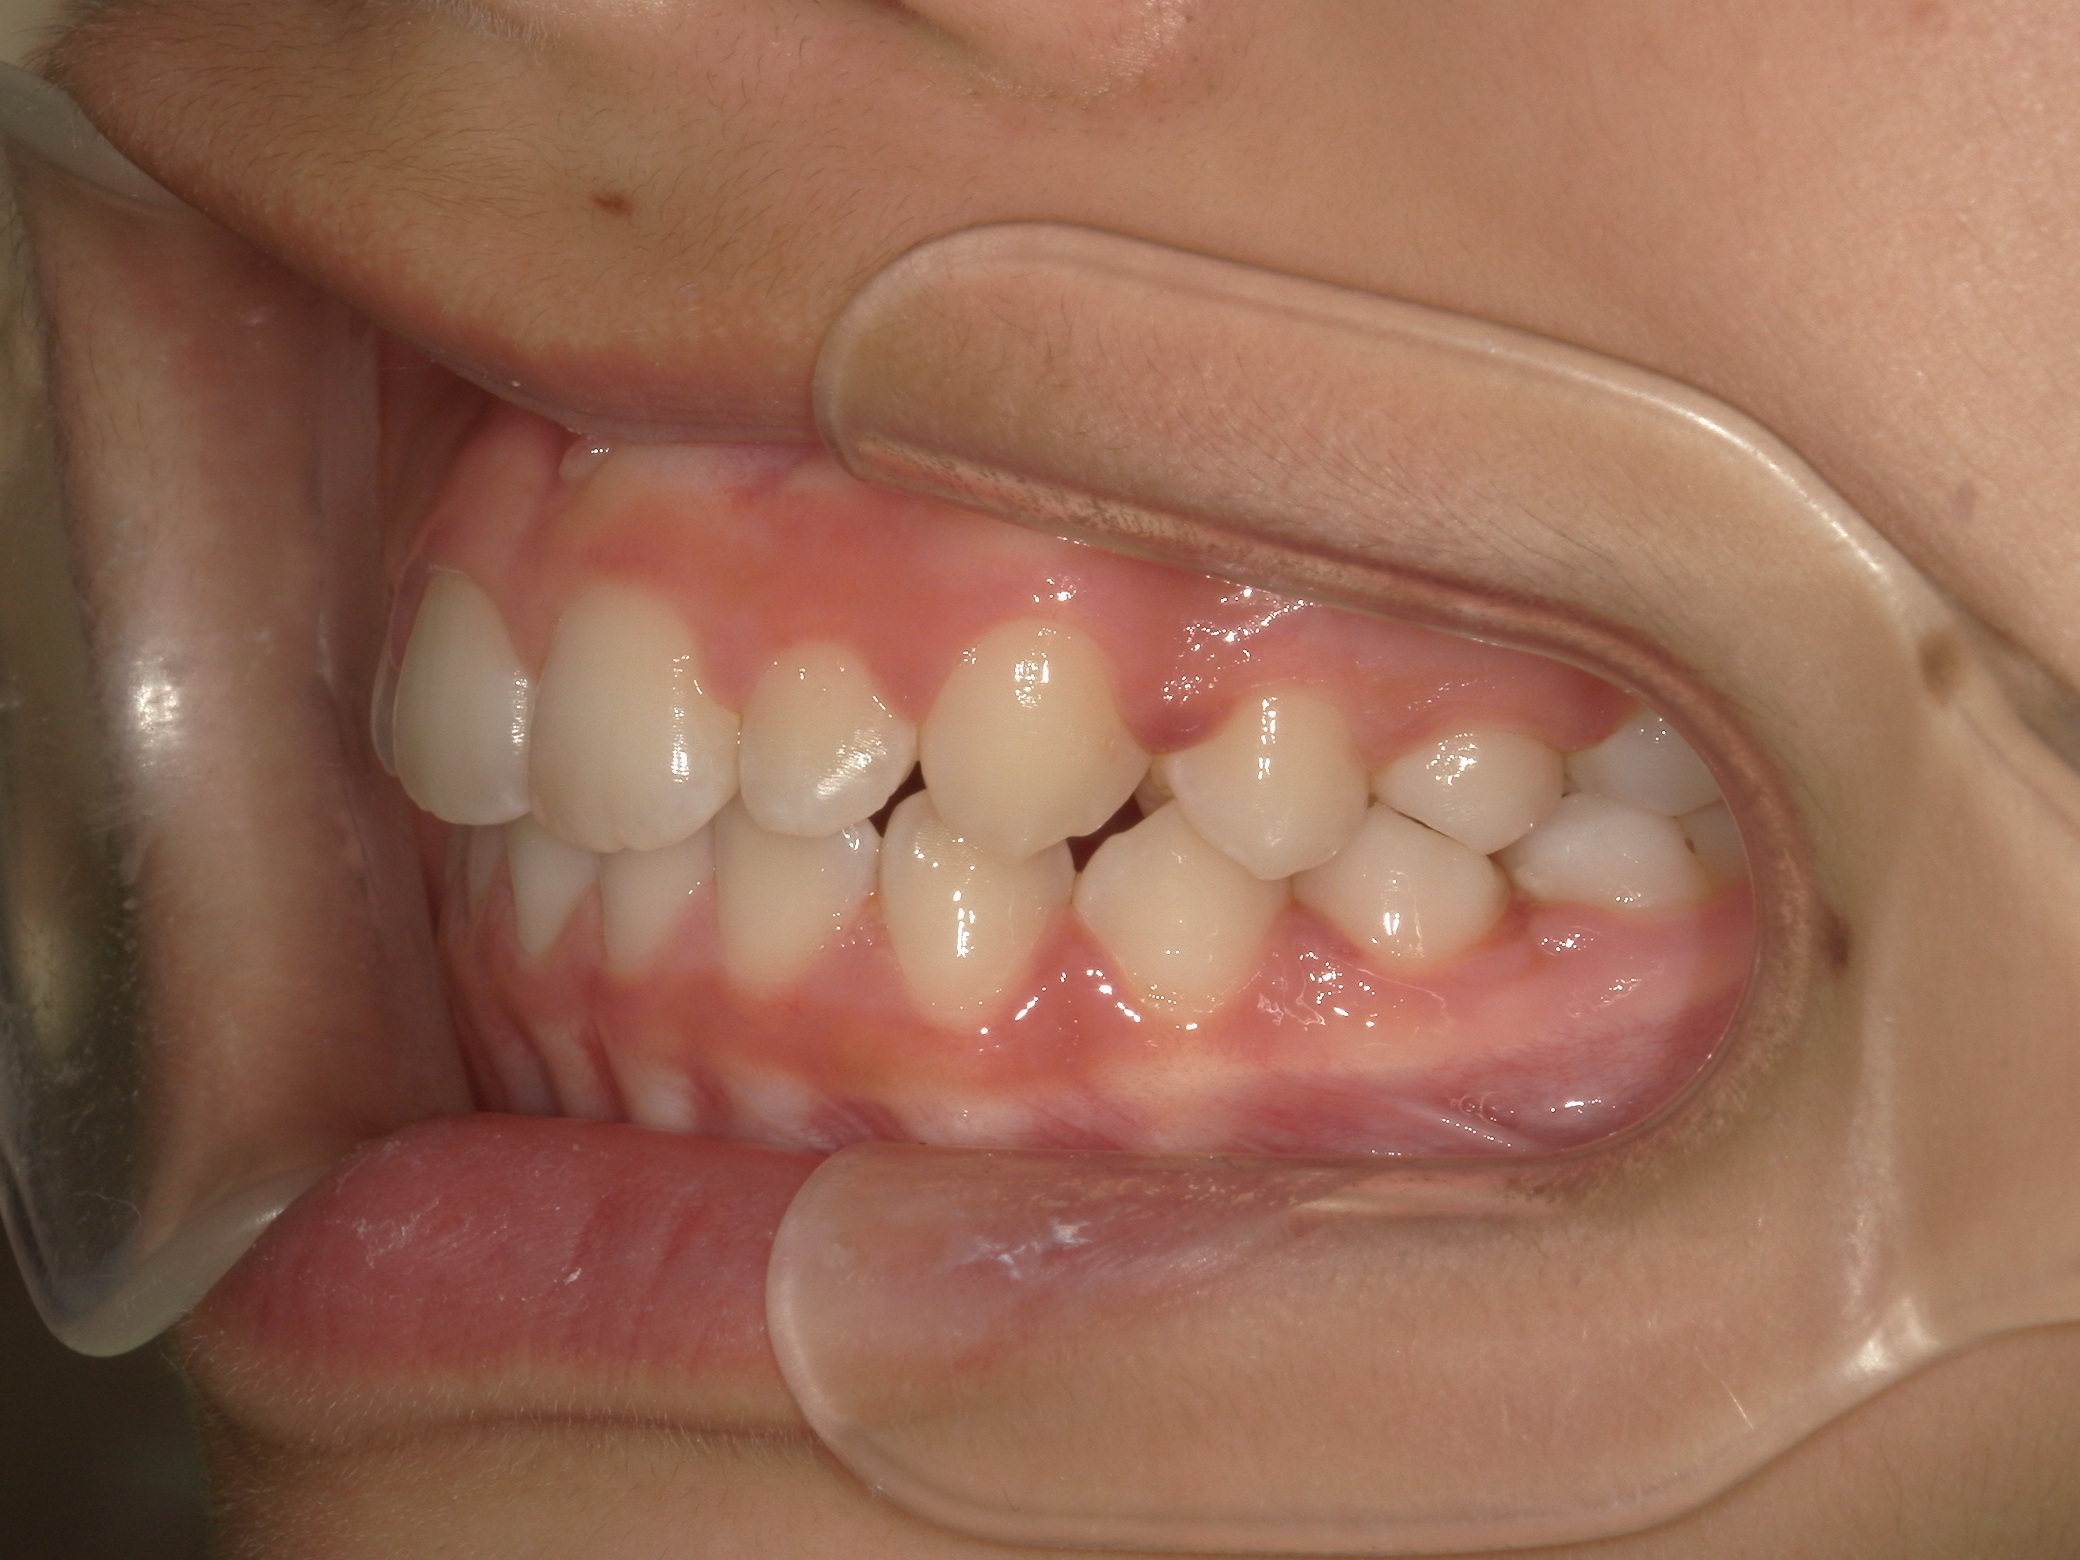

【小学生】 マイオブレース矯正 叢生(でこぼこ)を改善

小学生で開始

マイオブレース

でこぼこ

非抜歯

1期治療のみで改善

Before

After

治療期間

2年

治療開始

8歳

種類

マイオブレース矯正

使用装置

マイオブレース 3Dリンガルアーチ

コメント

非抜歯で 治療期間は2年

治療後4年たっていますが、綺麗な歯並びを維持しています